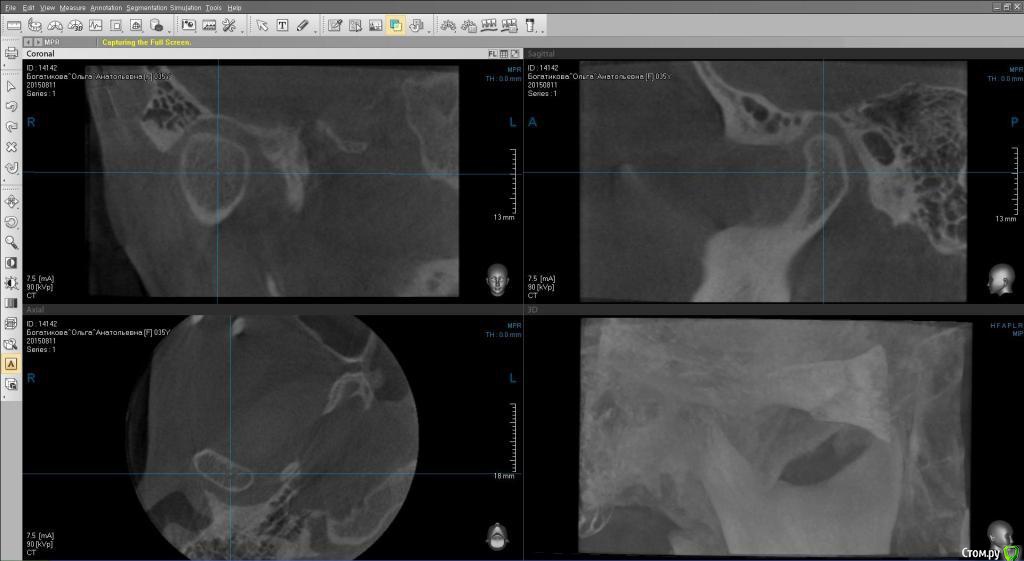

ol"ga Опубликовано 15 августа, 2015 Автор Поделиться Опубликовано 15 августа, 2015 (изменено) Вот еще кт левого и правого внчс, и фото улыбки Изменено 15 августа, 2015 пользователем ol"ga Ссылка на комментарий

Yana guapa Опубликовано 15 августа, 2015 Поделиться Опубликовано 15 августа, 2015 я не вижу у ВАс асимметрии лица, асимметрии верхней челюсти. А вот нижняя челюсть смещена влево, (это видно по ОПТГ и фото), вследствие чего произошло смещение дискав таких случаях обычно1. выравнивают зубные ряды ( с удалением восьмерок) 2. ставят нижнюю челюсть в правильное положение (различными способами, специальные пружины, эластики, форсус, твин форс и т.д.) каждый врач сам для себя выберает, что ему удобнее п.с. похоже что вверху слева ВАм удаляли восьмерку, нго оставили 1 корень. Ссылка на комментарий

Yana guapa Опубликовано 15 августа, 2015 Поделиться Опубликовано 15 августа, 2015 по снимкам - все итак понятно, без подписей.по "щечкам" - Вам скуловые кости никто не двигал, мягкие ткани ортодонт тоже не перемещал, так что это не в юрисдикции ортодонта. вот поворот нижней челюсти - это да, это видно и этим можно заниматься Ссылка на комментарий